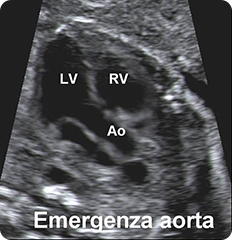

torace:

valutazione e visualizzazione della posizione del cuore e dei polmoni;

visualizzazione delle 4 cavità cardiache, dell'emergenza e incrocio dei

grossi vasi e della scansione 3VT